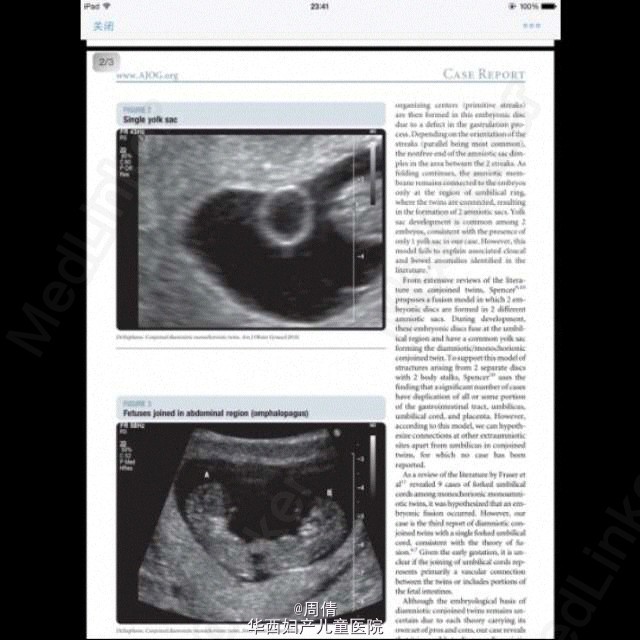

超声诊断单绒毛膜双胎羊膜囊融合一例

37岁女性,G3P1,自然受孕9w。 阴道超声示:子宫腔单个妊娠囊内2个胎儿,单绒毛膜。拥有共同的卵黄囊,在脐周相互连接。